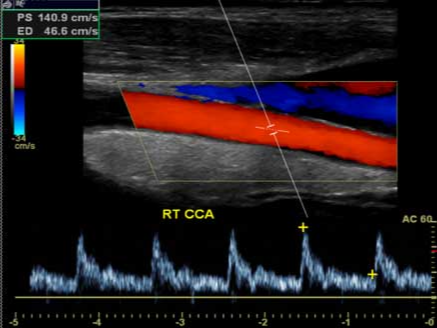

- 도플러 초음파: 혈류의 속도와 방향, 스펙트럼을 분석해 협착 정도를 정량화합니다.

죽상경화로 혈관 내강이 좁아지면 도플러에서 최고수축기속도(PSV) 상승, 난류, 스펙트럼 확산이 관찰됩니다. 중등도 이상의 협착은 뇌졸중 위험 상승과 연관되므로 항혈소판제, 스타틴 강화, 혈압·당뇨·지질 교정, 금연 등 집중적 위험인자 관리가 필요합니다. 특정 기준을 만족하는 중증 협착에서는 경동맥 내막절제술(CEA)이나 스텐트 삽입이 검토됩니다.

- PSV/EDV: 최고수축기속도/말기이완기속도. 협착이 심할수록 PSV 상승, EDV 변화 동반.